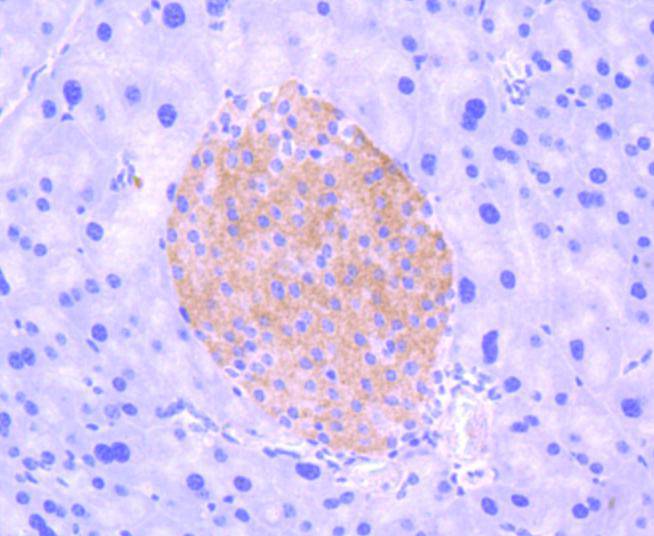

Formalin-fixed;paraffin-embedded mouse pancreas tissue stained for TrkB (Phospho-Y817) using 13384 at 1/100 dilution in immunohistochemical analysis.